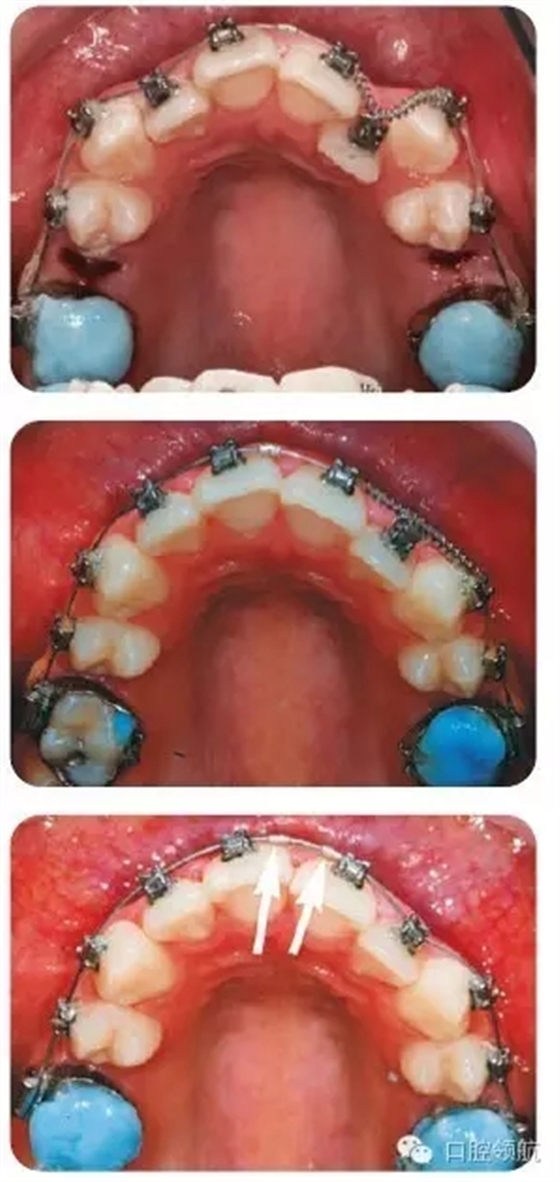

圖3.2中治療措施的說明

拔除上頜雙側第二前磨牙后,粘結上頜托槽,使用0.013英寸鎳鈦圓絲,配合UL1、UL3間的鎳鈦推簧,為UL2的納入提供間隙。同時,以上頜第一磨牙為支抗,采用彈性鏈狀結扎圈拉尖牙向遠中移動。UL2通過結扎絲懸吊至弓絲上,以促進其唇向移動。由于可能導致的牙弓變形,牙齒傾斜移動以及難以預估的反作用力,我們通常并不推薦在鎳鈦圓絲上使用主動力。但是,有研究指出自鎖托槽穩(wěn)定的鎖結效果可以有效地規(guī)避上述風險。

圖3.2(第三幅圖)中所示的箭頭是什么?

這是在弓絲上放置的小型金屬停止扣,用以阻止治療初期出現(xiàn)的弓絲滑脫。否則,由于自鎖托槽與弓絲間的滑動摩擦力過小,弓絲可能由一側滑脫,甚至刺入磨牙后墊造成損傷。

為什么在上頜第一磨牙面放置玻璃離子墊高材料?

這項措施能夠使上下頜脫離咬合接觸,從而有利于糾正UL2鎖。也可以使用活動矯治器或固定的咬合打開裝置達到此目的。